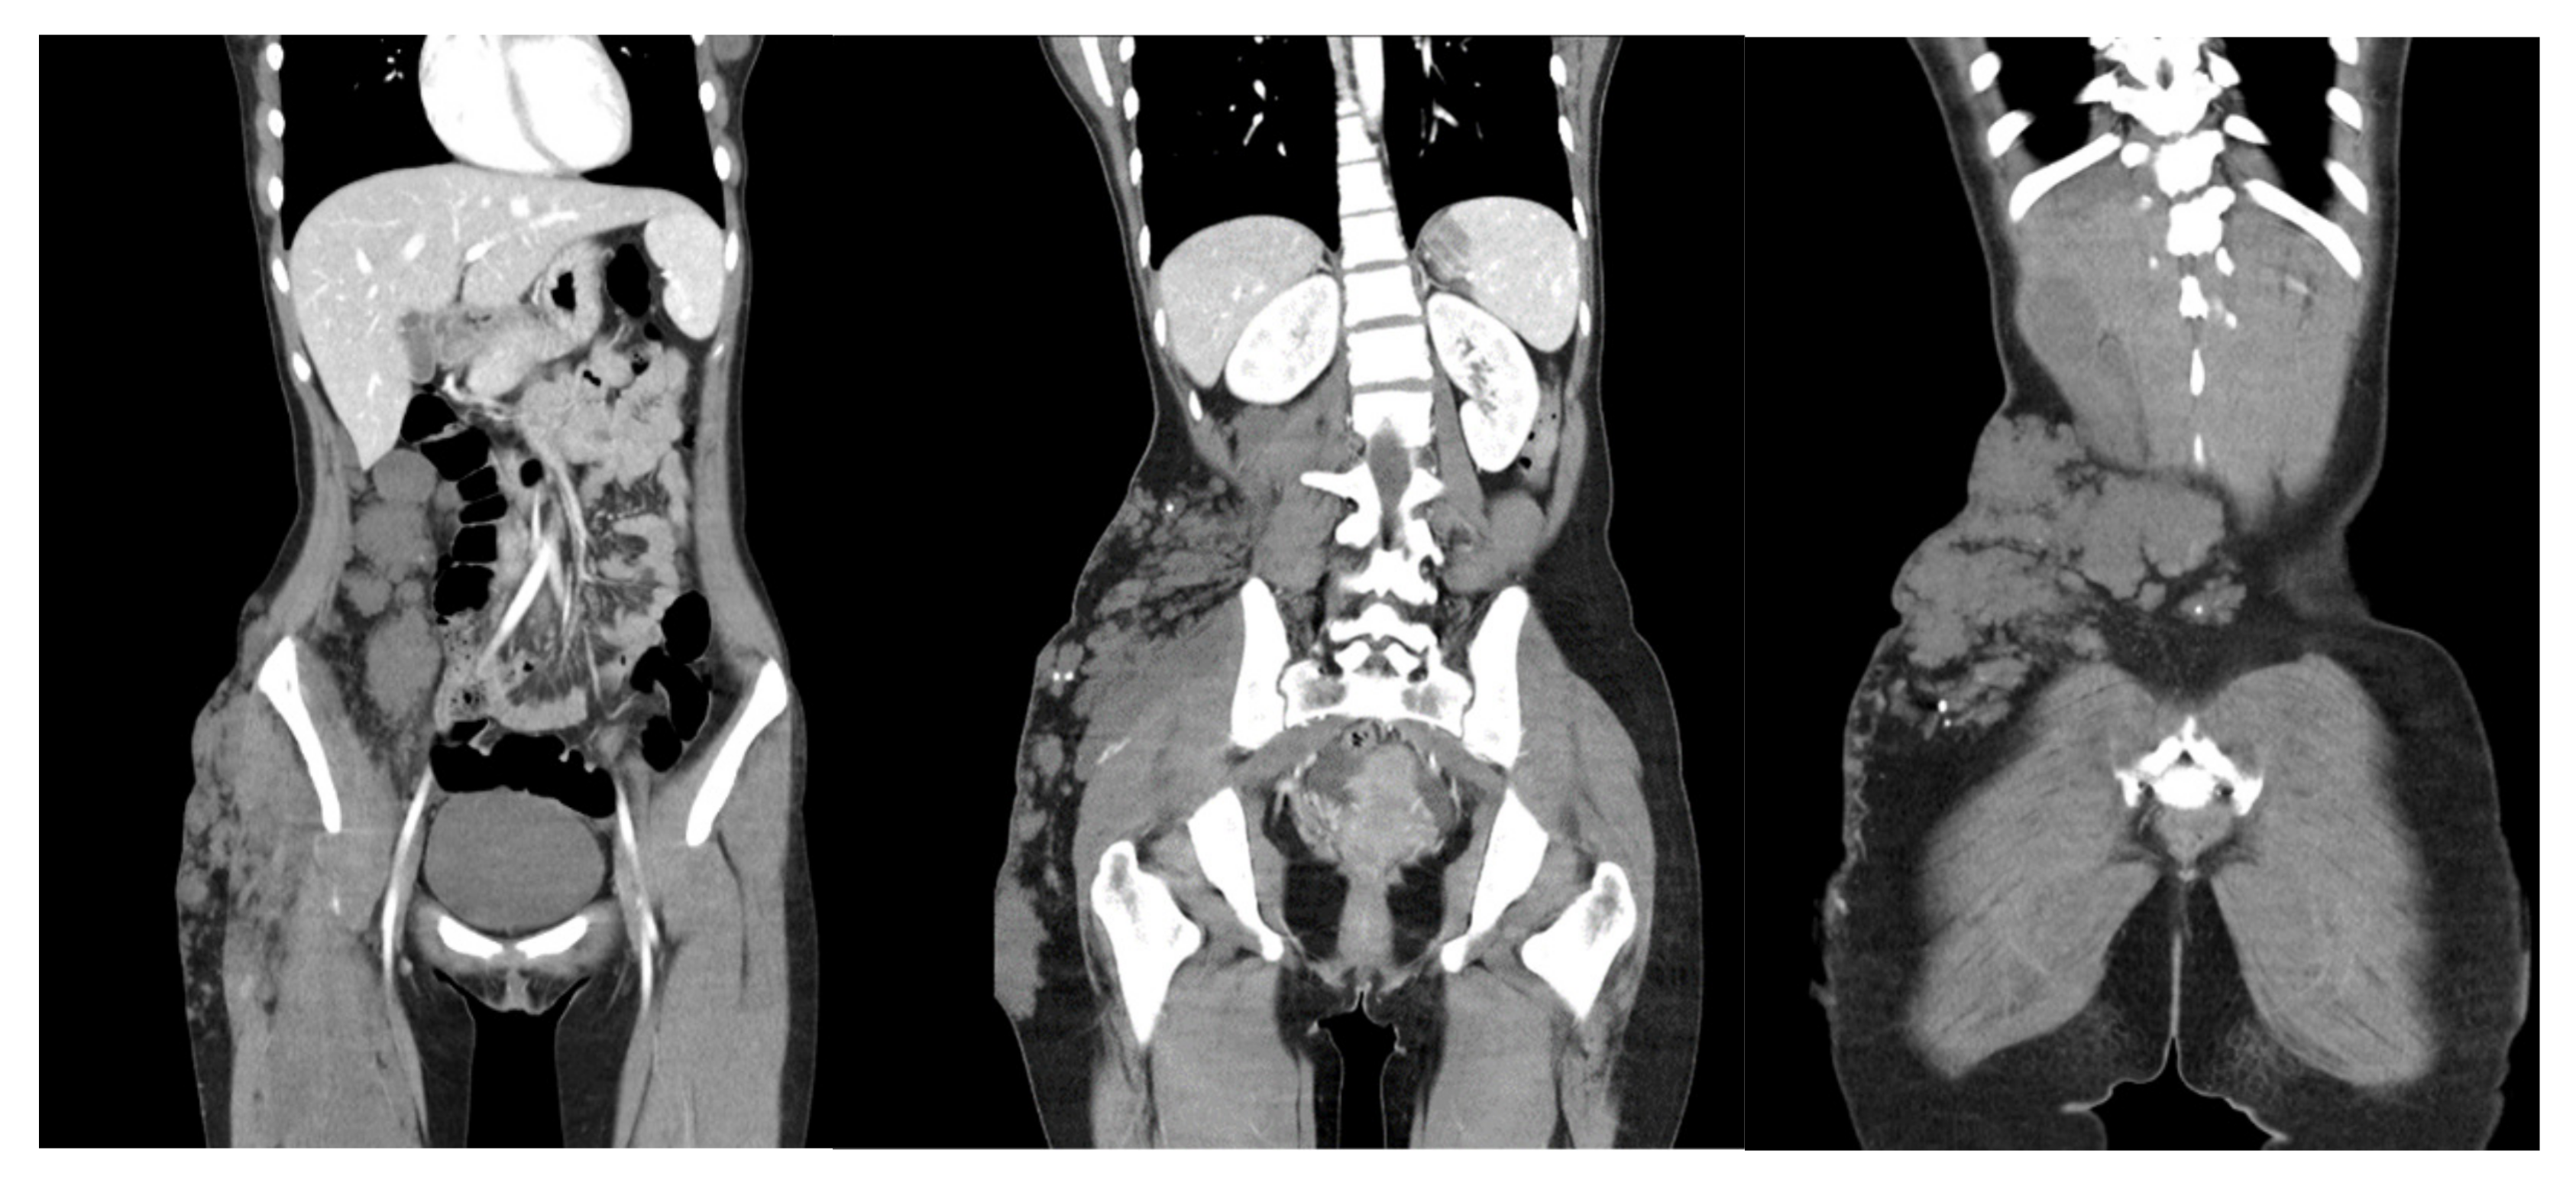

2. Case